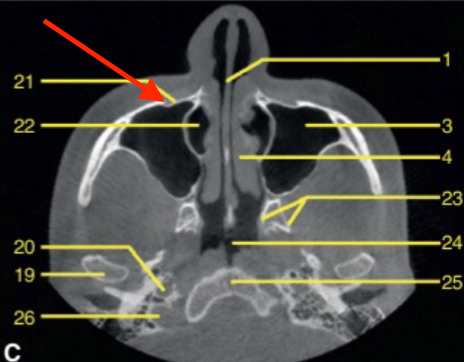

axial

what plane is this

level of maxilla (above maxillary teeth)

at what level is this